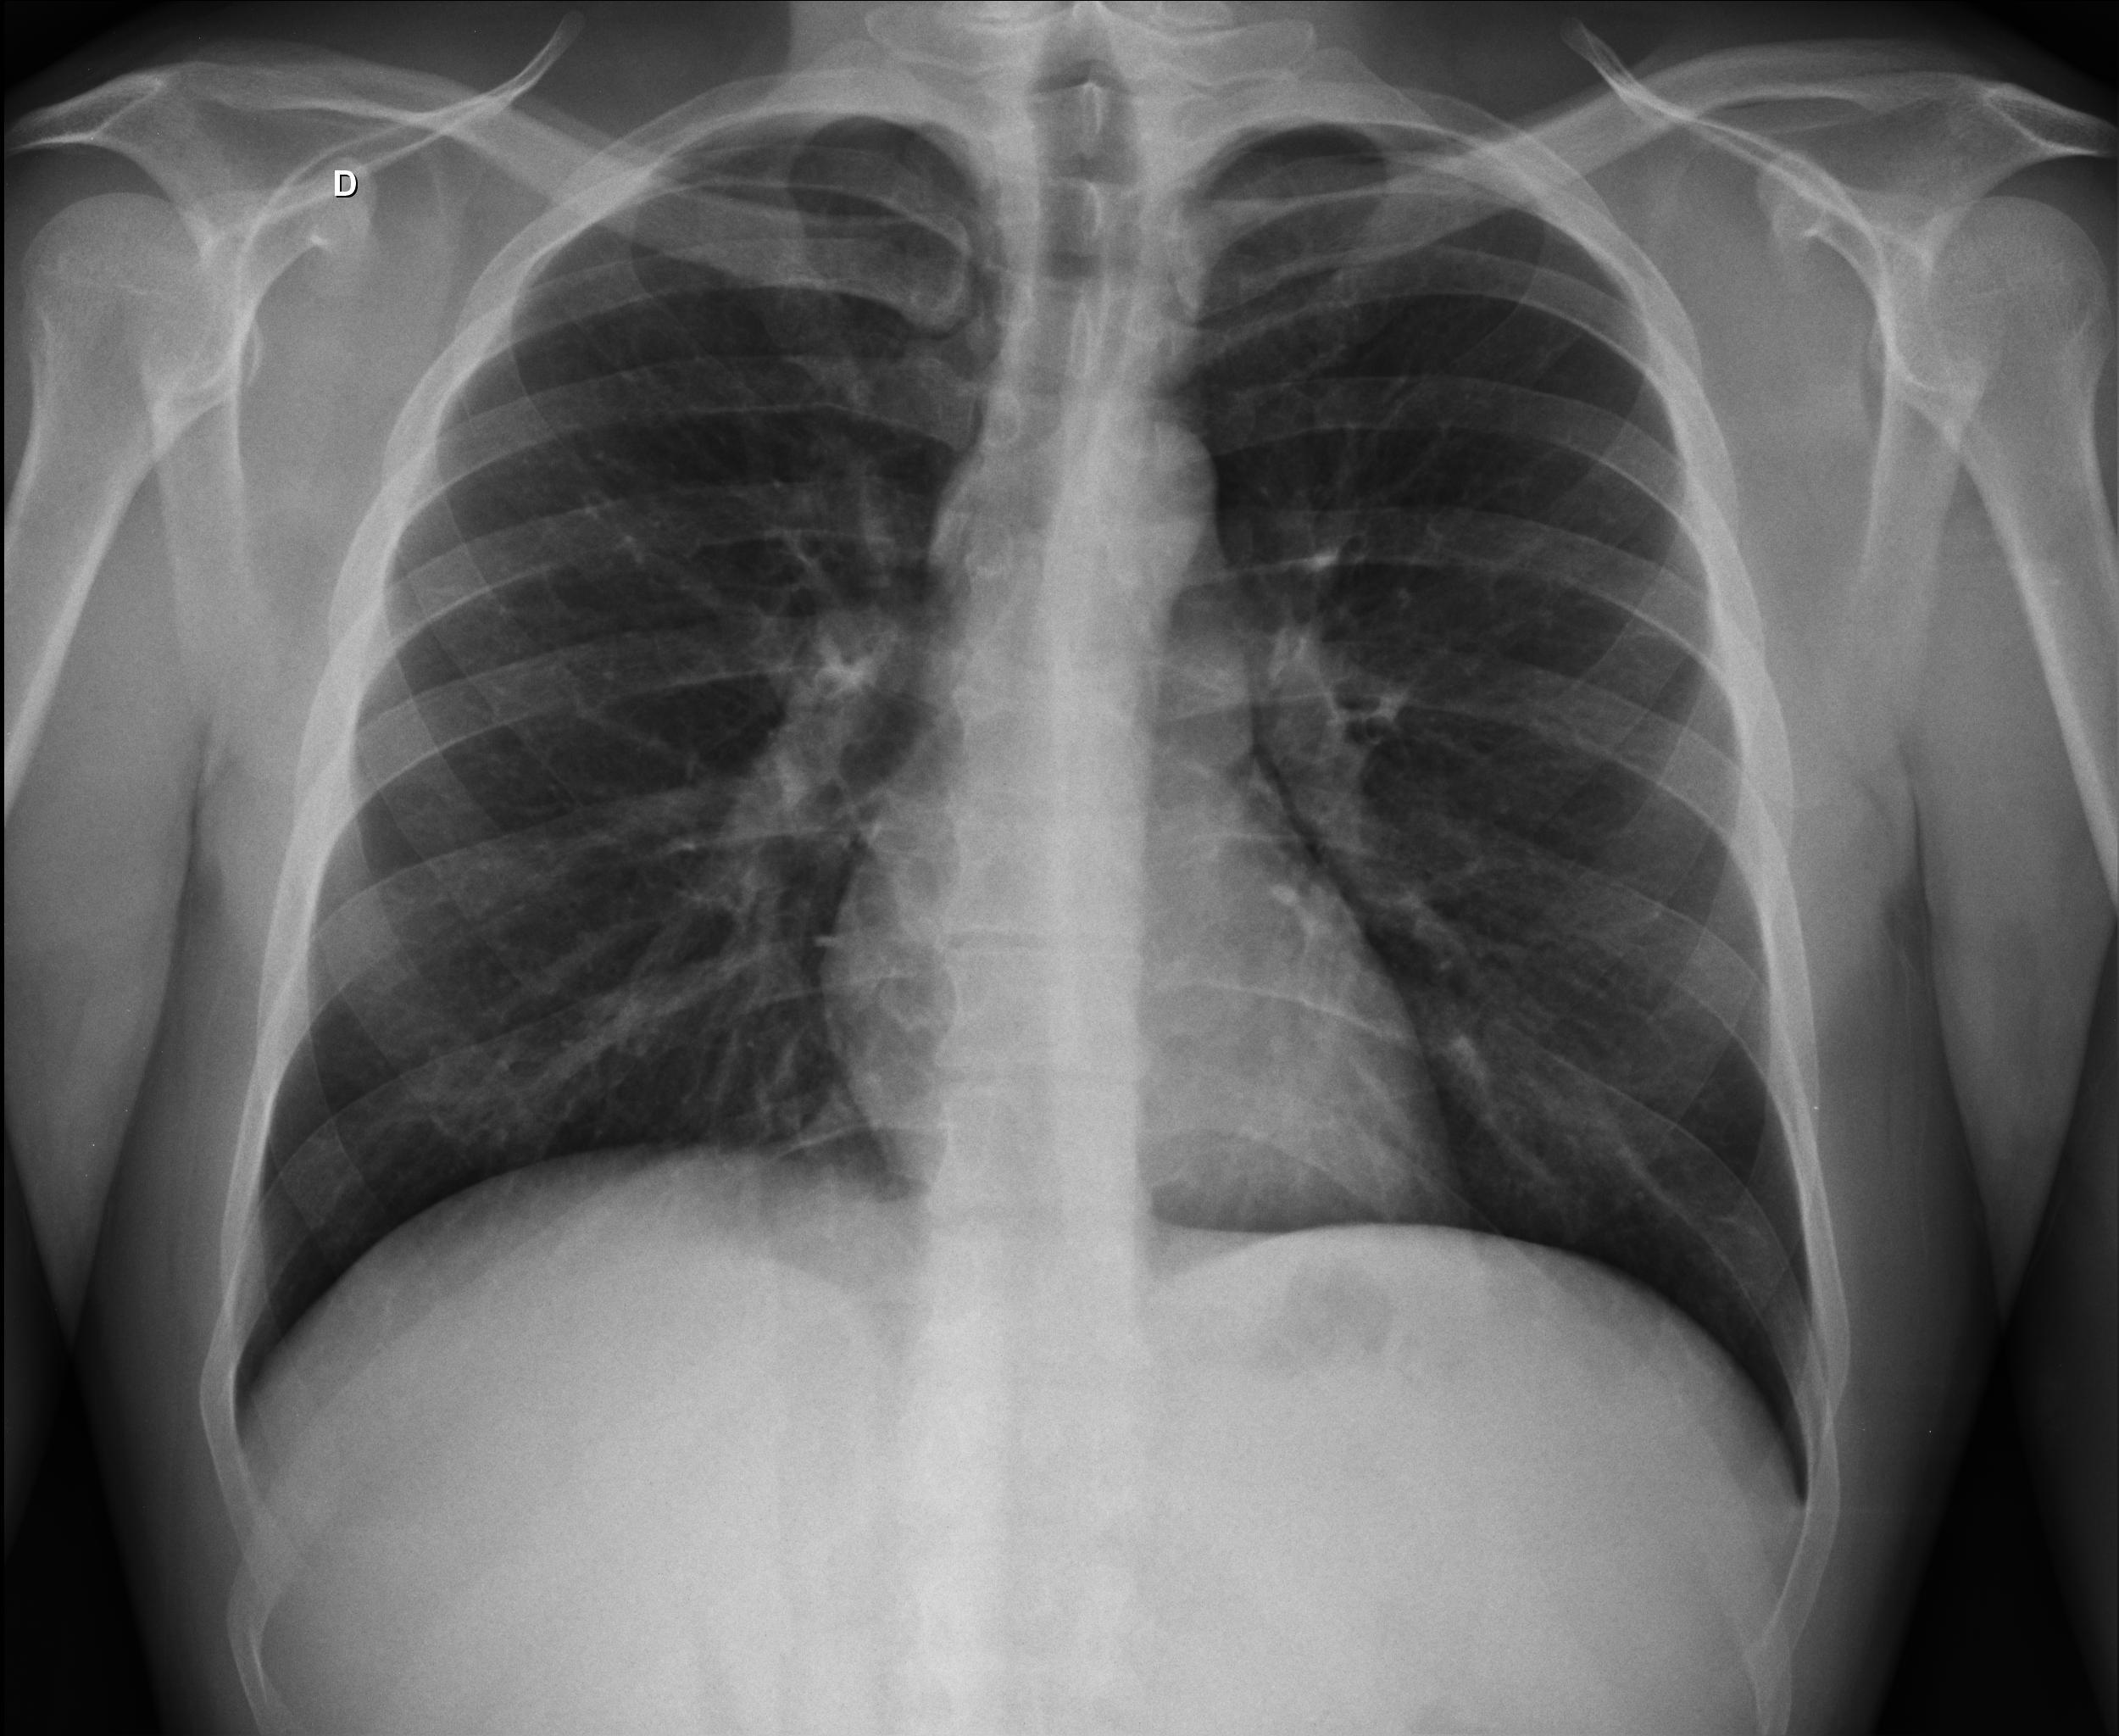

Caso Número 4/2018: “Uma sessão interativa de casos em radiologia torácica – Parte 1”

Caso relatado na Reunião de Discussão de Casos Clínicos do Hospital Universitário Prof. Polydoro Ernani de São Thiago, iniciada pelos Profs. Jorge Dias de Matos, Marisa Helena César Coral e Rosemeri Maurici da Silva, em julho de 2017. No dia 14 de junho de 2018, no auditório do HUPEST, realizou-se a apresentação e discussão do caso cujo registro é apresentado a seguir. Trata-se da discussão de onze casos em radiologia torácia, de forma interativa com a plateia, e assim ocorre também neste artigo.